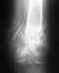

Здравствуйте, можно ли вылечить грыжу межпозвонковых дисков без операции?

Если грыжу межпозвонковых дисков можно вылечить только проведением операции, проводятся ли они в Вашем институте для жителей других областей, сколько ориентировочно стоит данная операция и какие документы нужны для обращения к Вам?

• Кликните для загрузки файла 15.jpg